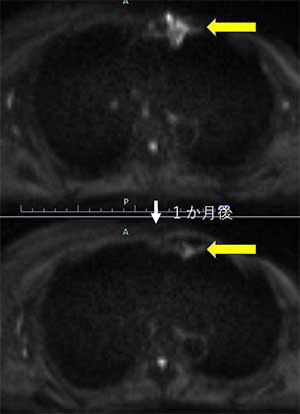

9月に行われた3例目はもともとCTなどでみえるより、広い範囲のPETの集積が認められた腫瘤より大きめに広がっている(播種している)患者さんです。

BNCT1か月後のMRIを示します。MRIでは縮小し、拡散強調画像でも効果が得られています。

本研究では腫瘍マーカーや拡散強調画像では効果判定を行わないため、また今後のMRIやCTで違う結果になる可能性があります。また現在のところいずれの患者さんでもGrade2までの副作用ですが、今後の過程では発生する可能性はあります。

また、皮膚に播種していた3例目ですが、下に5月後のPET-CTを示します。このように腫瘍の取り込みだけでなく、皮膚への播種病変への取り込みも無くなって、普通の放射線治療や粒子線治療(重粒子線や陽子線)と違ってBNCTでは播種に強い、というのが示されたかと考えております。(なお、PET画像はともに患者さんからのご厚意で掲載させていただいております)